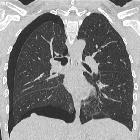

HRCT is the modality of choice for thoracic endometriosis, which may demonstrate presence of pneumothorax, hemothorax or nodules which may change in nature cyclically. There may sometimes be vague areas of bronchial wall thickening, thin-walled cavities, bullous formation or ground glass opacities. HRCT may also be used to provide guidance for targeted biopsy. Imaging should be carried out during menstruation for higher sensitivity.